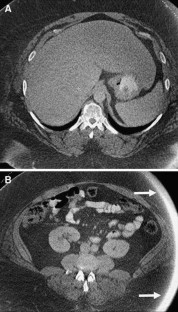

Fig. 4